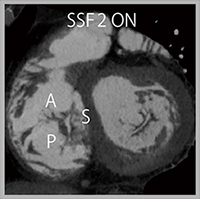

図3 症例3:三尖弁閉鎖不全症

症例3は,超音波にて弁尖同士の離開を認め,重度の三尖弁閉鎖不全症である。このような症例では通常,中隔尖と前尖の間に逆流口があることが多いが,本症例は経食道心エコーにて中隔尖と後尖の間に逆流口を認め,CTでも同様の所見であった。SnapShot Freeze 2を適用したことで,逆流口の輪郭をきわめて明瞭に描出可能であった(図3)。